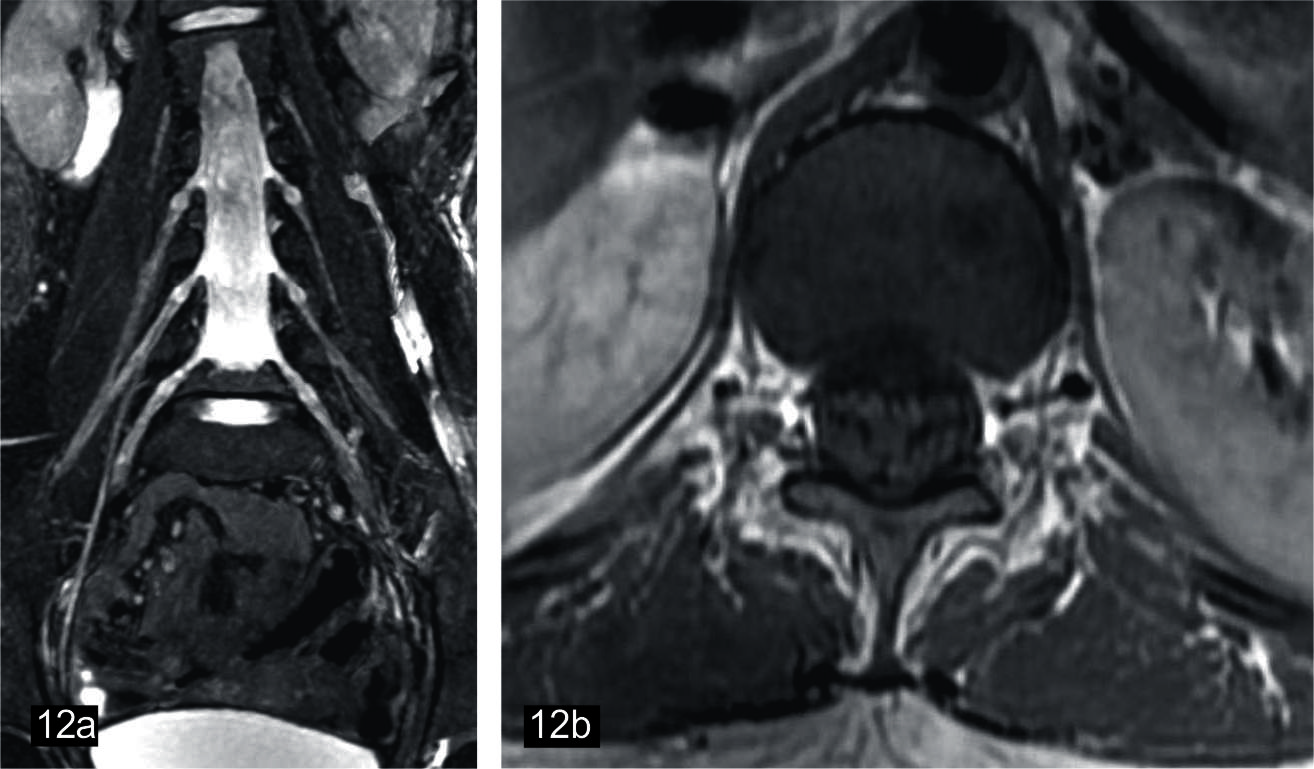

Figura 12

Sindrome de Guillain Barré en niño de 9 años

(a) Secuencia neurográfica IDEAL water en ponderación T2, que muestra engrosamiento e hiperseñal difusa de los ramos del plexo lumbar. Imagenes convencionales de columna en FSE ponderación T1 (b) axial con contraste, (c) sagital sin contraste, (d) sagittal con contraste, se observa engrosamiento y realce de raices de cauda equina.

El sindrome de Guillain Barré es la polineuropatía inmunomediada pos infecciosa más comun y es una urgencias neurológica (54). Las manifestaciones en NRM son variables en función de los nervios afectados. El hallazgo más frecuente es el el aumento de grosor y el realce pos contraste de las raíces de la cuada equina (55). Sin embargo, también se describe la afectación de plexos y con menor frecuencia de pares craneanos, los cuales se observan hipertrofiados y pueden presentar realce pos contraste. La neurografía también es de utilidad en el control de las lesiones conocidas (56). (Fig. 12).